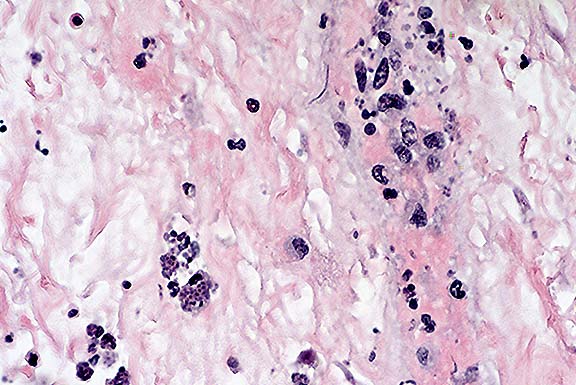

Case 8-3. Stomach. Within a vessel wall in the submucosa, there are many extracellular banana-shaped Toxoplasma gondii zoites with scattered mixed leukocytes (vasculitis). An intracellular protozoal cyst containing numerous zoites is also present (lower left). 40X

Contributor's Diagnosis and Comments: Acute diffuse necrotizing gastritis with intralesional tachyzoites (Toxoplasma gondii and canine distemper virus infection).

The stomach is characterized by coalescing to diffuse mucosal and submucosal necrosis with hemorrhage and marked submucosal edema. Glandular epithelial cells are pyknotic or reduced to cell debris. There is necrosis of vascular walls in the submucosa. The lamina propria and submucosa are diffusely infiltrated with neutrophils, macrophages, and fewer plasma cells. Gastric epithelial cells and smooth muscle cells contain numerous tachyzoites within the cytoplasm. Numerous extracellular tachyzoites are free within the lamina propria and submucosa, and monocytes within blood vessels contain tachyzoites. Tachyzoites associated with focal areas of necrosis were also present in liver, pancreas, adrenal gland, spleen, pancreas, lung, brain and myocardium